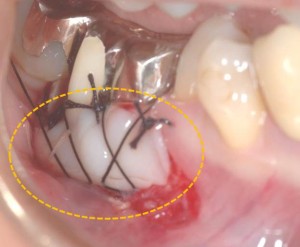

上顎裏側の緑○部分より移植し、創傷治癒材でカバーしています。

オレンジ○の部分が移植後2ヶ月になります。